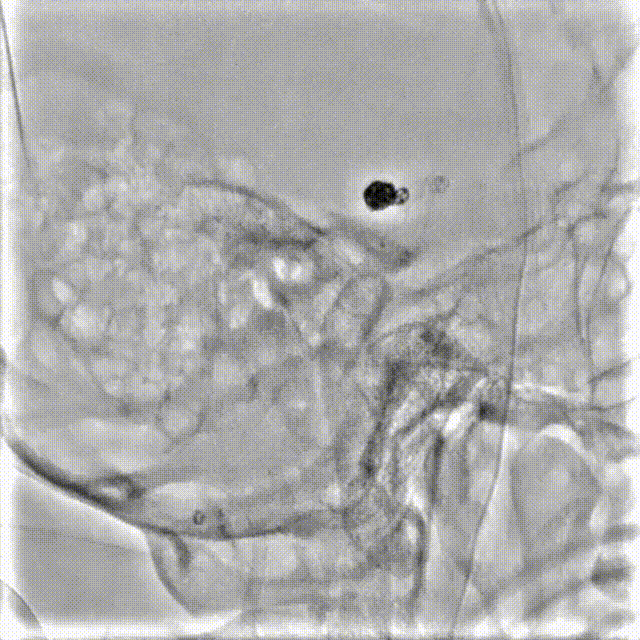

输送并完全释放第一枚Orbit Galaxy水解圈4mm*6cm。

接续送入第二至四枚Orbit Galaxy水解圈3mm*8cm、3mm*8cm、2.5mm*5cm。

最后一枚水圈疏松填塞,造影观察分支血管血流良好,结束栓塞。透视下观察支架和弹簧圈状态,支架贴壁良好。

术后工作位造影。

术后正侧位造影。

透视下旋转观察。

透视下检查支架情况,打开良好,贴壁良好。

术后CT重建显示支架贴壁良好。